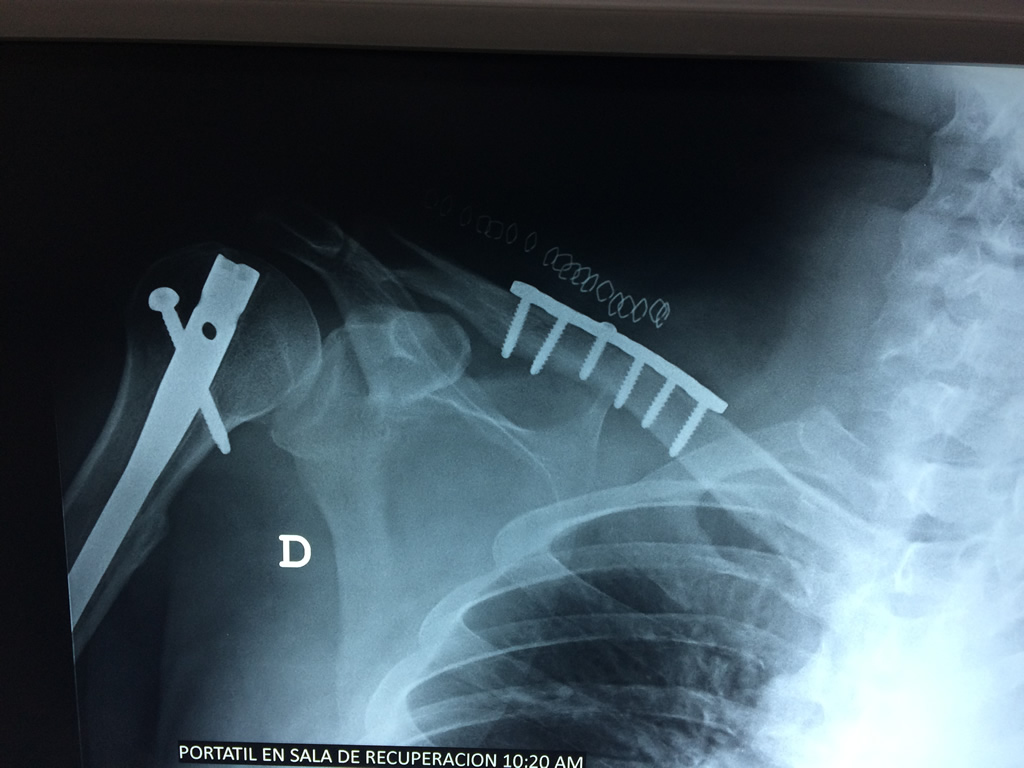

Clavícula

La clavícula es un hueso largo, con forma de "S" itálica, situado en la parte anterosuperior del tórax. Junto con la escápula forman la cintura escapular. Se puede palpar por toda su longitud y se extiende del esternón al acromion de la escápula, siguiendo una dirección oblicua lateral y posterior.